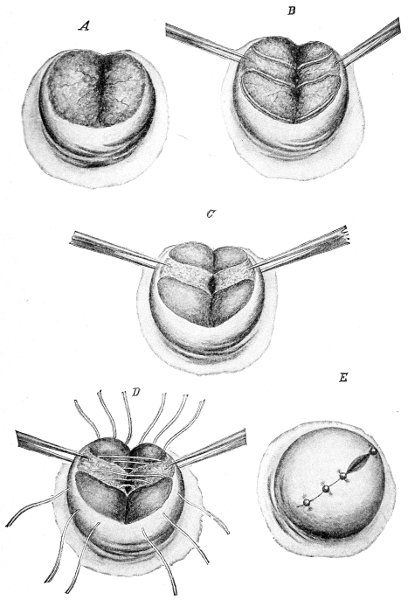

If the laceration extends up the posterior vaginal wall, two sets of sutures must be introduced—one on the vaginal aspect of the tear, and one on the skin aspect (Fig. 35).

Slight Median laceration of the Perineum.—In this injury the tear takes place through the fourchette. Posteriorly it may extend as far as the sphincter ani muscle. Upward it may extend for an inch up the posterior vaginal wall. The appearance of this tear is shown in Fig. 33. It will be noted that, as this tear takes place in the median line, none of the muscles that support the perineum are involved, nor are the planes of fascia injured. The perineum is slightly split, and the insertions and origins of the muscles and the fascia are slightly separated. The supporting structures of the perineum and the pelvic floor are, however, uninjured.

Fig. 33.—Recent slight median laceration of the perineum: sutures introduced.

If this tear is detected after labor, it should be closed by the immediate operation. A slight tear involving chiefly the cutaneous aspect of the perineum should be closed by three or four sutures introduced from the outside, as in Fig. 33. The needle should be introduced about a quarter of an inch from the edge of the wound. It should not be passed parallel with the plane of the lacerated surface, but should be swept outward and then inward toward the 68 angle at the bottom of the tear (Fig. 34). It may either emerge at the angle and be re-introduced, or it may be passed directly through to the skin-margin on the opposite side of the wound. If the suture is passed in this way, there will be perfect apposition throughout the whole surface of laceration. If the sutures are improperly passed, there may result only apposition of the skin-edges.